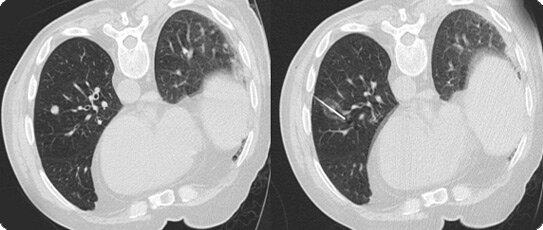

A range of innovative ablative (locally destructive) therapies are available at UCH and RNOH, which can be used in conjunction with other treatments such as chemotherapy and radiotherapy. These include radiofrequency ablation of liver, lung and soft tissue metastases, and vertebroplasty to strengthen bones in the spine weakened by cancer. These therapies allow destruction of a tumour using energy delivered to the tumour though fibre-optic probes placed into the tumour. The procedure is carried out under sedation or a short general anaesthetic. It allows patients to have tumours treated without having large operations.